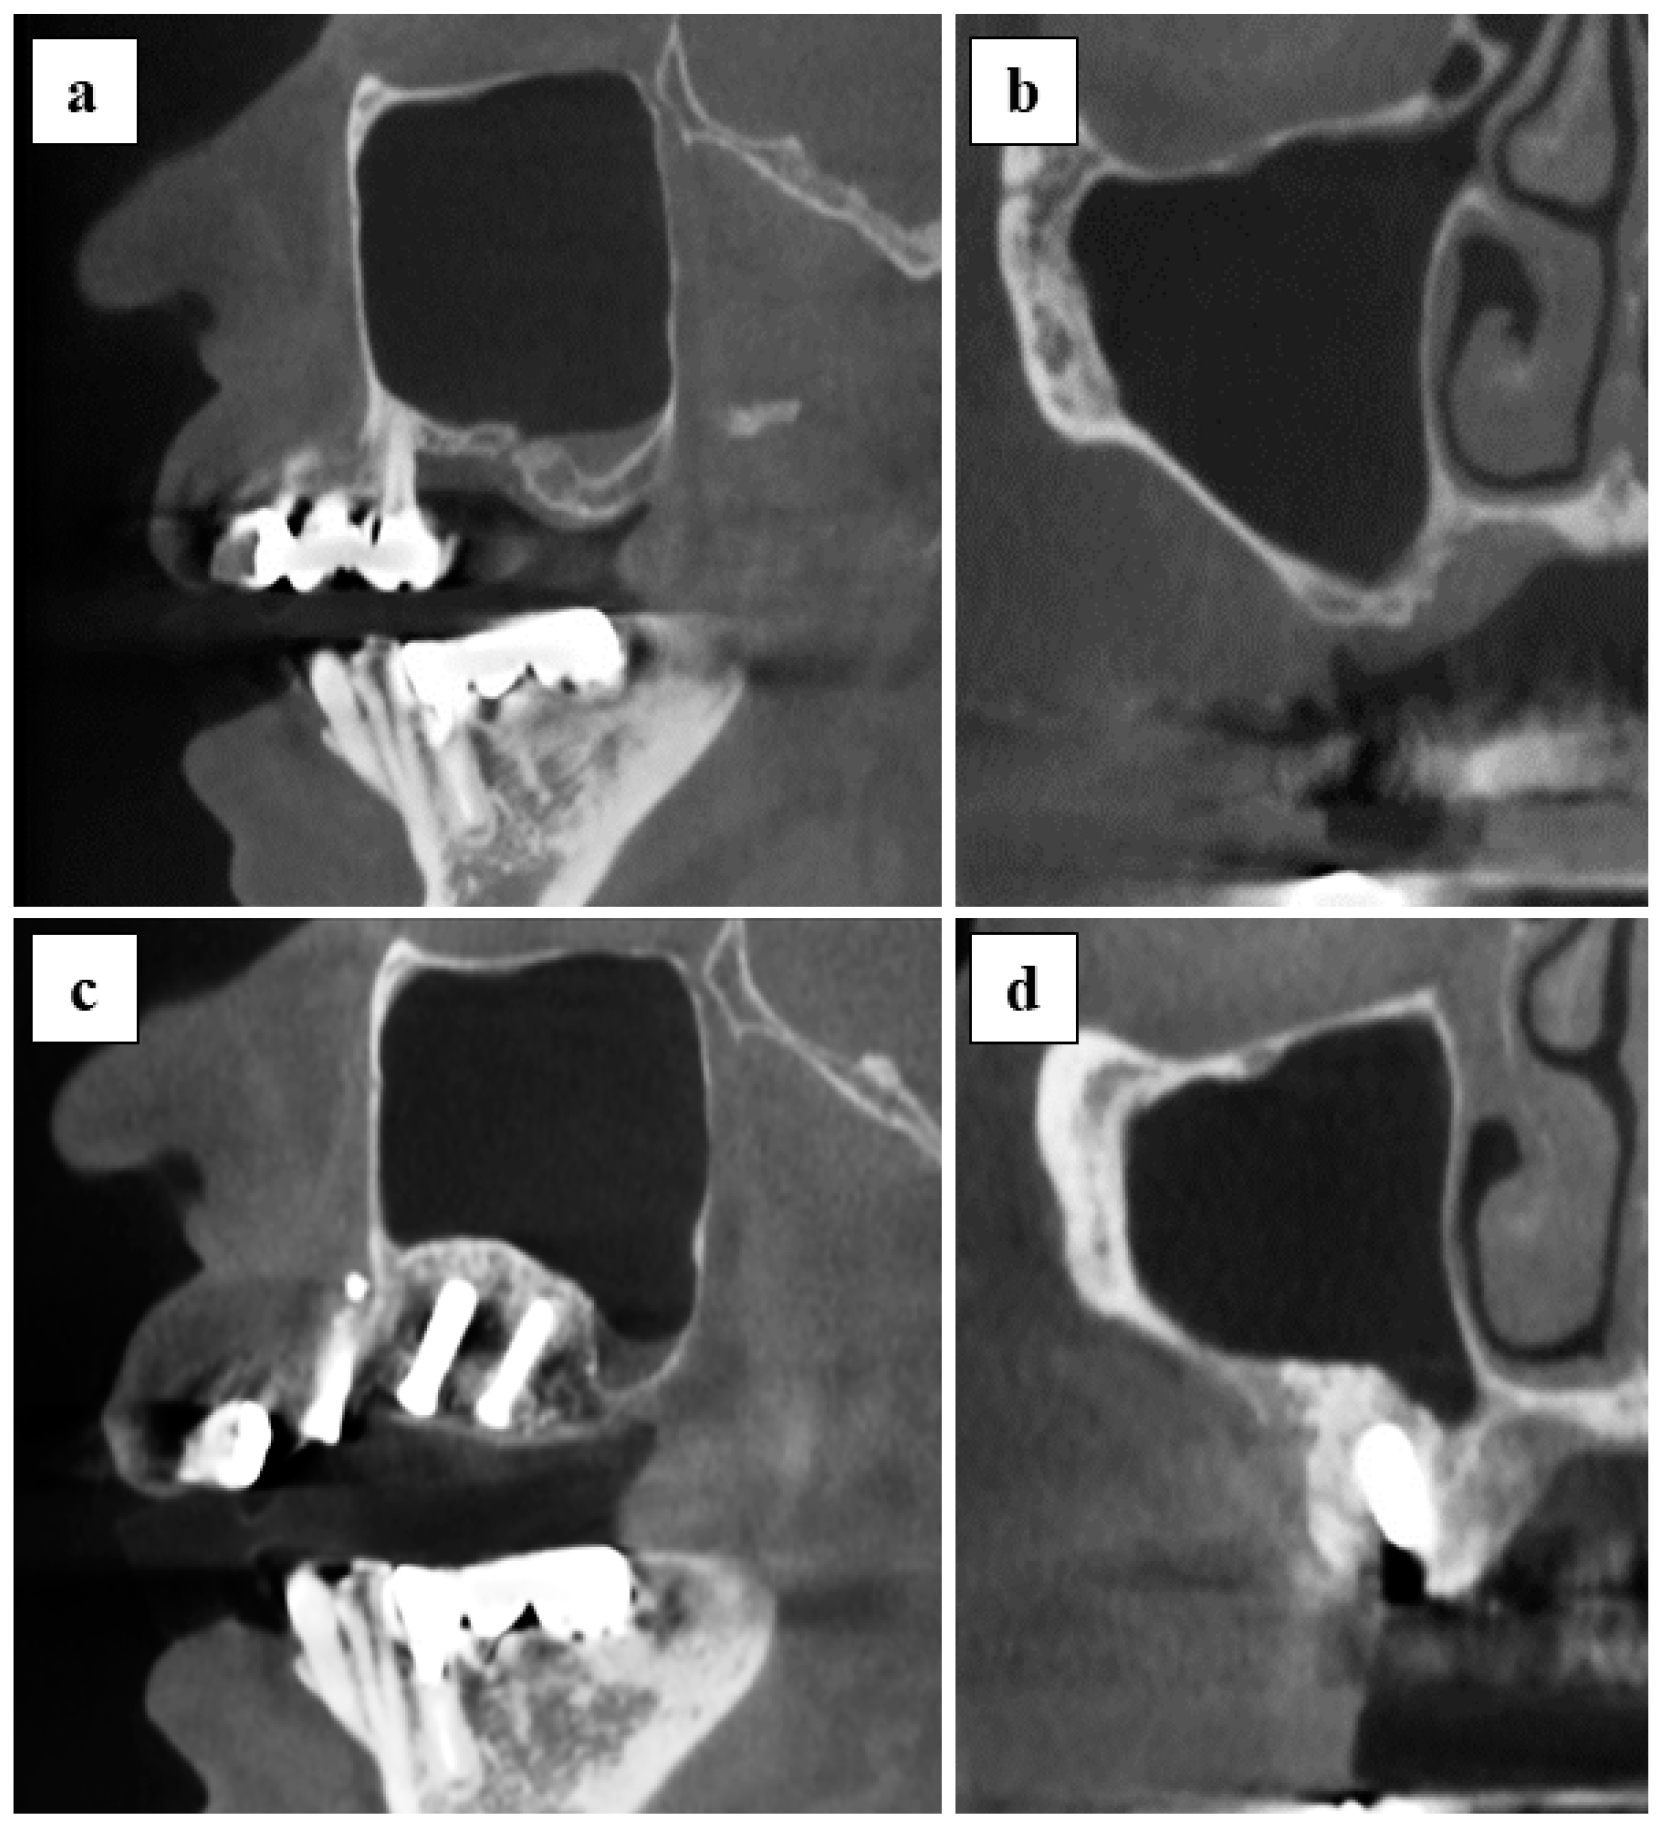

3.4. Radiographic Assessment and Implant Stability

The vertical bone height at the transplanted site was quantitatively measured from panoramic findings (Figure 4). The mean of vertical bone height at the pre-operative stage and post-operative stage at day 1, 1 month, and 6 months was 3.7 ± 1.0, 10.0 ± 3.8, 9.6 ± 3.5, and 9.0 ± 3.6 mm, respectively. A significant difference was observed between the pre-operative stage and each of the post-operative time-points. Evidence of maxillary sinusitis or other complications was not found in all cases from the CT findings of 6 months post-operatively (Figure 5).

In the simultaneous approach group, there were 5 implants in 3 cases. There were no cases in which there was implant loss. The mean ISQ level was 73.6 ± 4.1 with a range of 70–80 at 6 months after surgery. (Table 3)

The second concern was to assess the efficacy of applying x3FD-PRP for bone regeneration. The usage of FD-PRP in bone engineering is currently being investigated for a wide range of therapeutic indications across multiple fields in laboratory studies and through animal experimentation. For instance, Shiga et al. reported that FD-PRP maintained baseline levels of growth factor for an entire 8-week duration [6] and that FD-PRP accelerated bone formation with artificial bone used in a rat posterolateral fusion model [13]. Kinoshita et al. reported that PDGF in FD-PRP is pharmacologically active in vitro after 4 weeks of storage [14]. It is also reported that FD-PRP significantly enhanced alkaline phosphatase activity and the mRNA expression level of osteogenic genes in vitro, and also that FD-PRP with scaffolds induced significantly greater bone formation compared to the traditional PRP in a rat calvaria defect [15]. In our previous study, FD-PRP promoted identical levels of bone formation as flesh PRP, and x3FD-PRP induced a more abundant bone formation on a mice calvaria onlay graft model [9]. In the current study, vertical augmented height was maintained for 6 months post-operatively (Figure 4) and initial stability of the implants was achieved (Table 3) without maxillary sinusitis (Figure 5). Specific evaluations of bone regeneration, such as bone biopsy or dense observation with a CT image, were not performed in this study, since the primary outcome of this study was safety verification. Based on previous studies and our results, the freeze-drying and storage process may not exert a negative impact on PRP to promote bone regeneration.

Figure 5. CT findings of pre-operative and post-operative at 6 months are shown: (a,b) pre-operative images, sagittal section and coronal section; (c,d) post-operative 6 months images, sagittal, and coronal section.